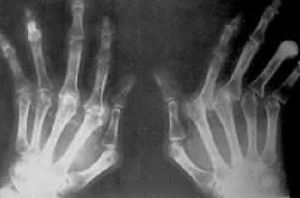

急性發作期僅見受累關節周圍非對稱性軟組織腫脹;反覆發作的間歇期可出現一些不典型的放射學改變;慢性痛風石病變期可見單鈉尿酸鹽晶體沉積造成關節軟骨下骨質破壞,出現偏心性圓形或卵圓形囊性變,甚至呈蟲噬樣、穿鑿樣缺損,邊界較清,相鄰的骨皮質可膨起或骨刺樣翹起。重者可使關節面破壞,造成關節半脫位或脫位,甚至病理性骨折;也可破壞軟骨,出現關節問隙狹窄及繼發退行性改變和局部骨質疏鬆等。